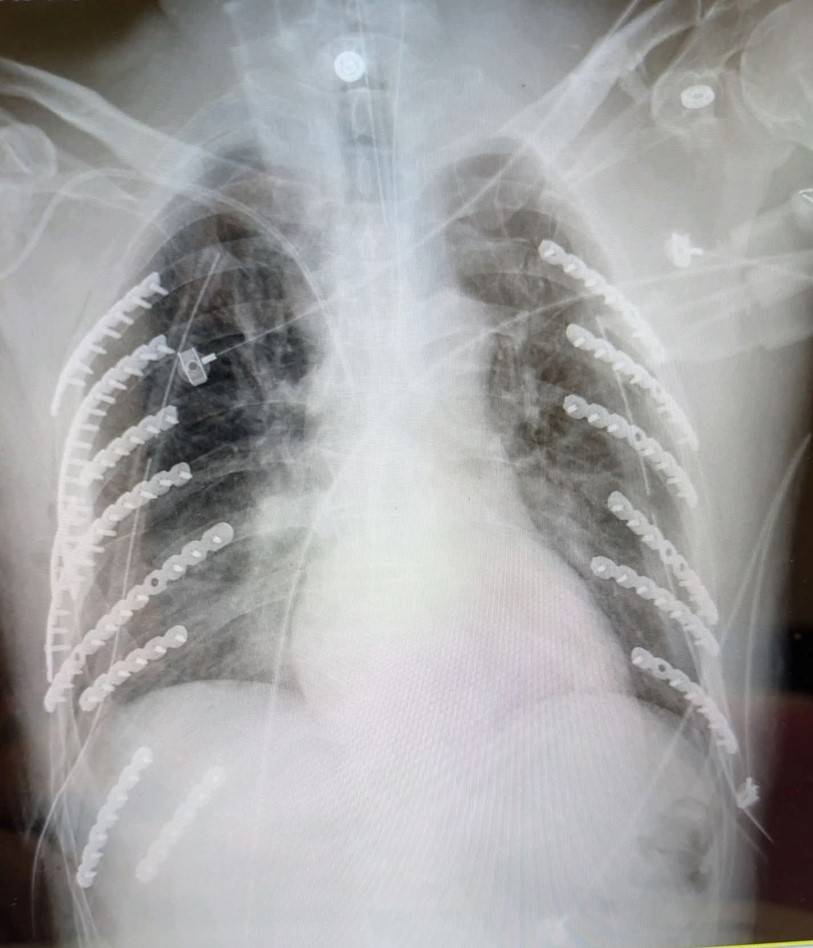

衛生福利部臺中醫院胸腔外科何蕙如醫師表示,患者第一時間被送往最近的急救醫院先插上胸管,確認生命跡象穩定後轉送到院,X光片顯示,雙側同時遭擠壓導致兩側共兩對二十八根肋骨,他就斷了十四根肋骨,甚至一根肋骨斷好幾截,比一般外傷平均斷裂三到五根嚴重許多;另外還合併左側鎖骨及部分脊柱裂傷,以及呼吸衰竭需插氣管內管,病況危急。

斷裂肋骨數量雖多,幸好未穿刺血管,在加護病房評估生命跡象穩定後,決定分兩階段手術。何蕙如醫師說,第一次植入八根、第二次植入六根鈦合金鋼骨,使肋骨復位固定,術後患者恢復良好,住院三周順利自己走著出院。他還自嘲身上十四根鈦合金,從此變成「鋼鐵人」,跟穿古代金鐘罩一樣厲害。